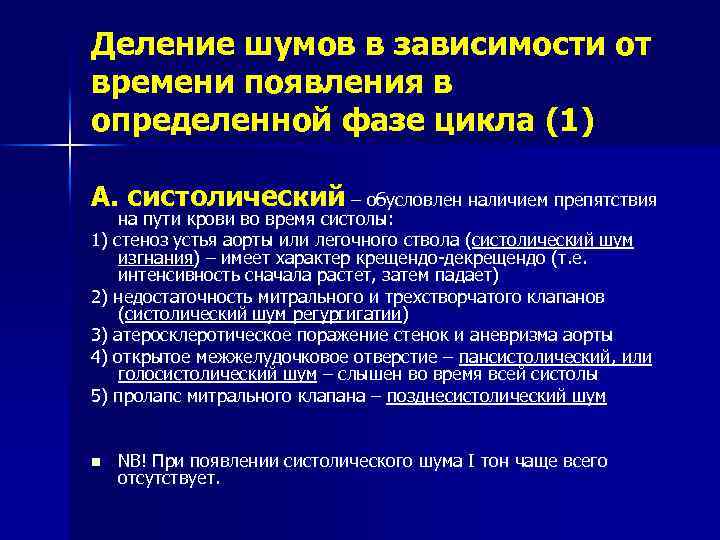

Деление шумов в зависимости от времени появления в определенной фазе цикла (1) А. систолический – обусловлен наличием препятствия на пути крови во время систолы: 1) стеноз устья аорты или легочного ствола (систолический шум изгнания) – имеет характер крещендо-декрещендо (т. е. интенсивность сначала растет, затем падает) 2) недостаточность митрального и трехстворчатого клапанов (систолический шум регургигатии) 3) атеросклеротическое поражение стенок и аневризма аорты 4) открытое межжелудочковое отверстие – пансистолический, или голосистолический шум – слышен во время всей систолы 5) пролапс митрального клапана – позднесистолический шум n NB! При появлении систолического шума I тон чаще всего отсутствует.